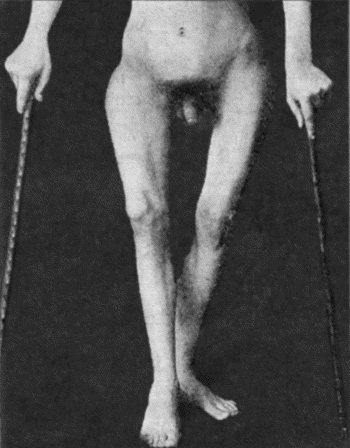

| 41. | Ulceration in inherited Syphilis | 170 |

| 127. | Advanced Tuberculous Disease in Region of Ankle | 459 |